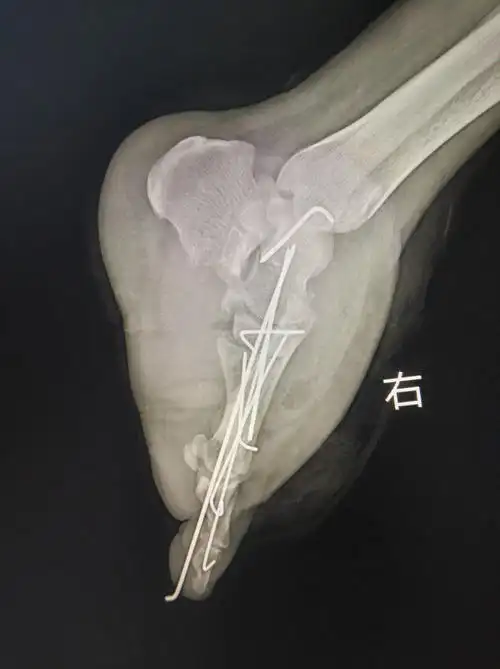

一个足部毁损伤的保肢过程